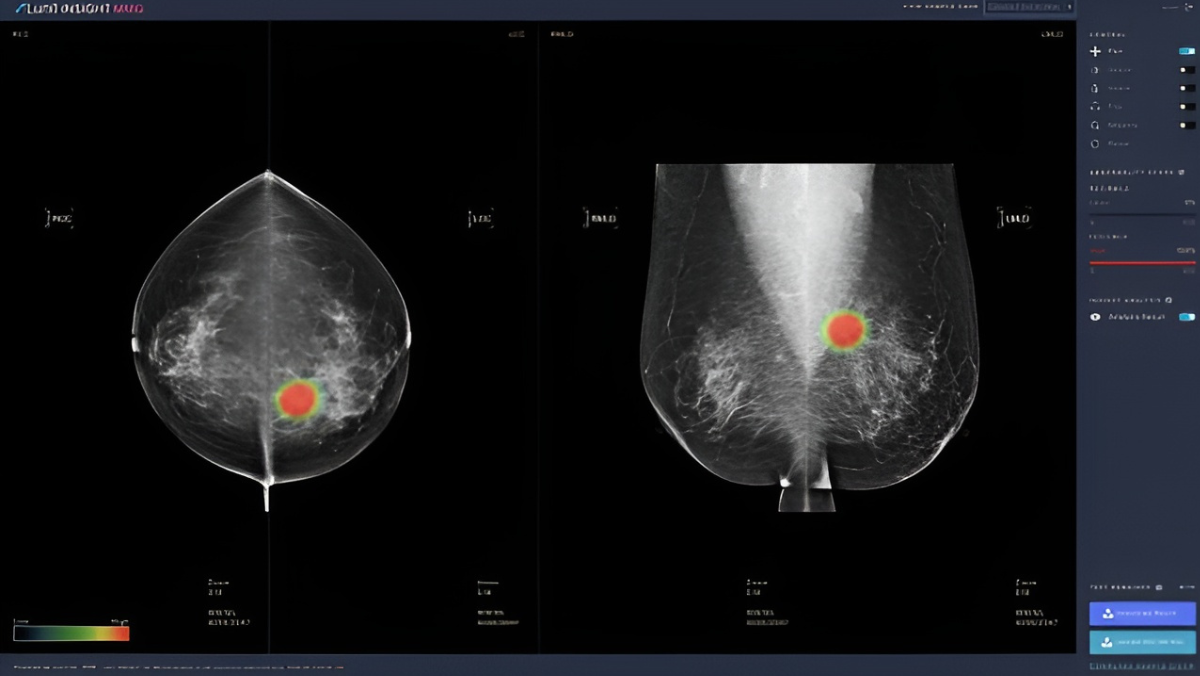

US regulators have approved the first artificial intelligence system that estimates a woman’s five-year breast cancer risk using data from a routine mammogram, marking a significant step in the use of predictive imaging in preventive care. The decision, issued through the Food and Drug Administration’s De Novo pathway, is seen by clinicians as an early sign that screening strategies may shift toward more data-driven assessment.

The system, Clairity, analyses patterns within breast tissue that may be difficult for radiologists to detect. It generates risk estimates without relying on genetic screening or family history, a feature that has attracted interest from large hospital networks seeking more precise ways to identify patients who may benefit from earlier or more frequent imaging.